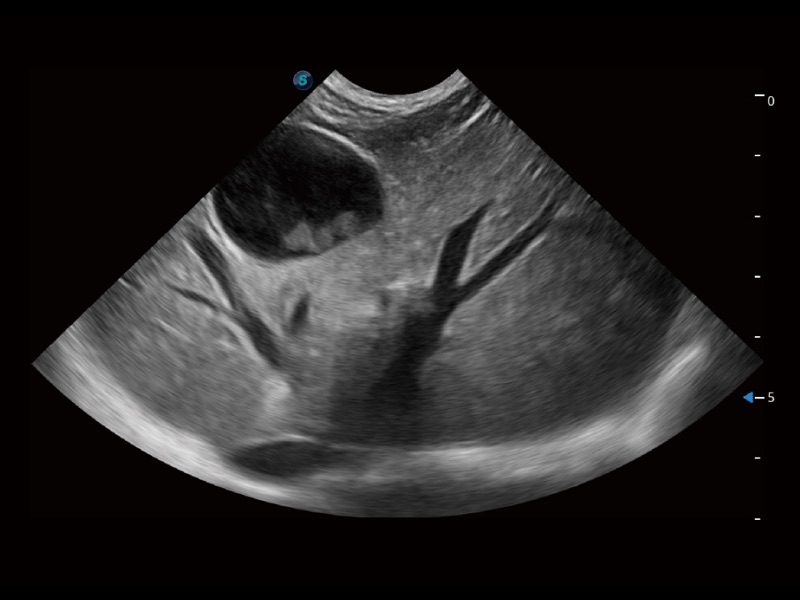

大型犬、马科、农场动物及大型异宠动物

通过创新的 Matrix E自适应滤波器和超长时间域算法,极大提升超低速微细血流的检出能力,同时更精准地滤除软组织和噪声信号,为兽用医生提供以往无法通过常规血流获得的疾病诊断信息。